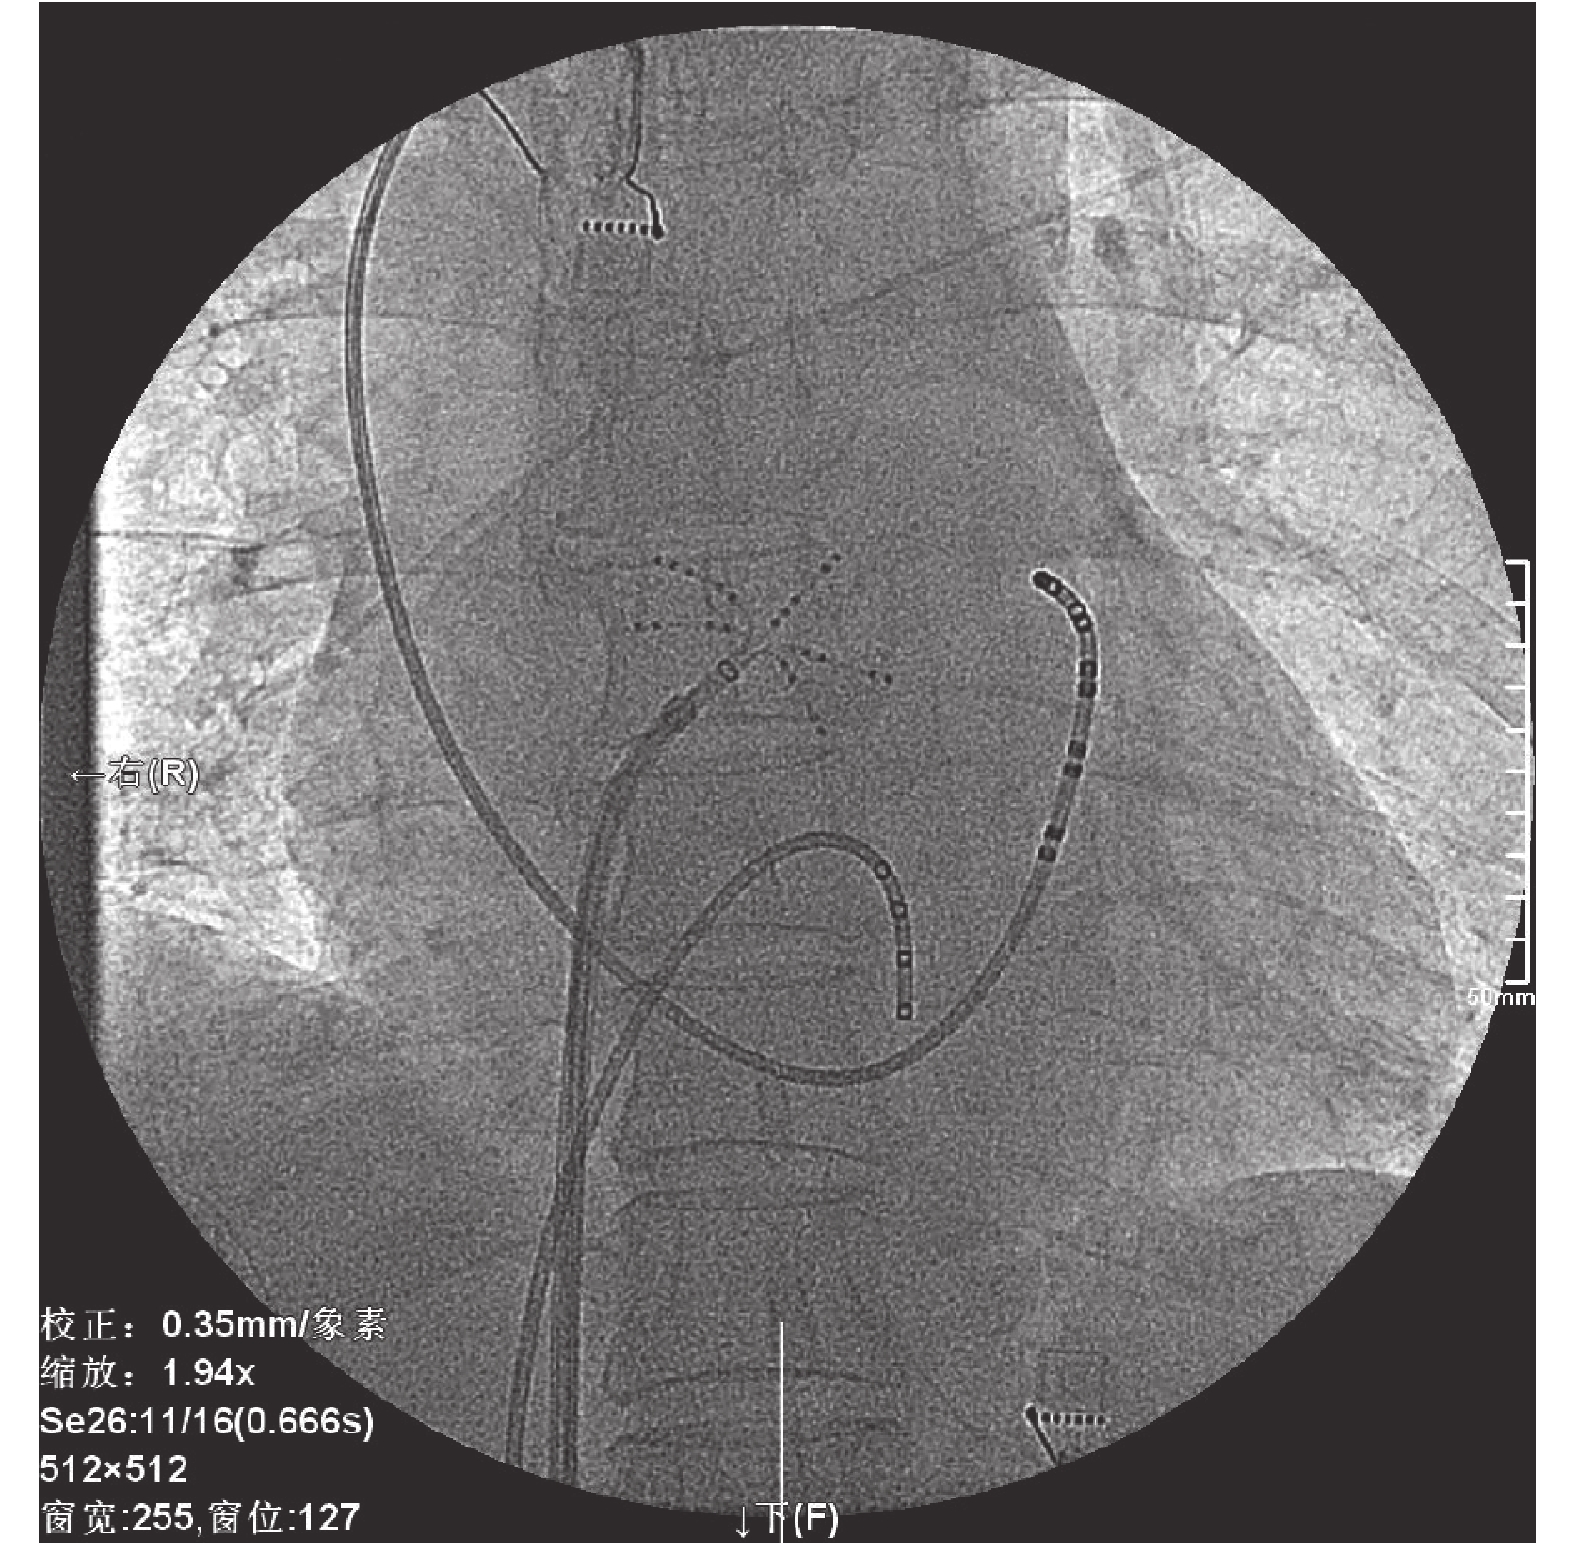

患者及家屬在充分了解應用 Pentaray高密度標測導管行心臟高密度標測及導管消融術后,簽署導管消融同意書。術前行碘過敏試驗為陰性。術前禁飲禁食 8 h。局部麻醉下,穿刺右側股靜脈及左鎖骨下靜脈,置入擴張管及鞘管。分別放置標測電極至右心室及冠狀竇。行電生理檢查示:左心房大折返性房性心動過速。局部麻醉下穿刺右側股靜脈,按程序放置鞘管,穿刺房間隔,在三維電解剖標測系統(Catro)及 Pentaray 高密度標測導管指導下標測示:左心房頂部依賴房性心動過速,行頂部線性消融成功(圖 1~3)。Lasso 電極在左心耳起搏,檢測左心房頂部線成功阻斷。觀察 15 min,電刺激無復發,退出電極,拔出鞘管,局部壓迫止血,紗布包扎穿刺點,術中患者無不適。于 2015 年 10 月 23 日好轉出院。術后隨訪 1 個月,患者無心律失常復發。

消融過程房性心動過速終止